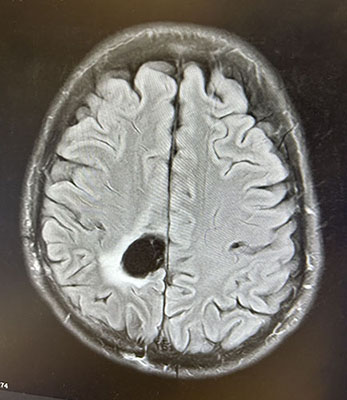

At Mass General Brigham Cancer Institute, Cory met with neurosurgical oncologist Daniel Cahill, MD, PhD, and neuro-oncologist Nancy Wang, MD, MPH. As they explained, an MRI scan showed Cory had a glioma—the most common brain tumor in adults.

"At Mass General, we see hundreds of glioma patients every year," he said. "Cory's tumor looked different than the most commonly seen gliomas and had features suggesting it might be an oligodendroglioma. 'Oligos,' as we call them, are rare. About 1 in 15 patients who have signs of glioma on their MRI scan will have an oligo."

The central portion of Cory's oligo was the size and shape of a lime, with wispy, tentacle-like extensions at the margins. Dr. Cahill's goal was to safely remove the main mass, leaving the remaining tendrils to be treated via radiation and chemotherapy.

Accessing and removing the tumor would be a delicate process. It was located underneath the part of the brain wiring that controls leg function. Each time Dr. Cahill took out a sliver of the tumor at the edge of this region, he and his colleagues tested leg function to confirm no damage had been done.